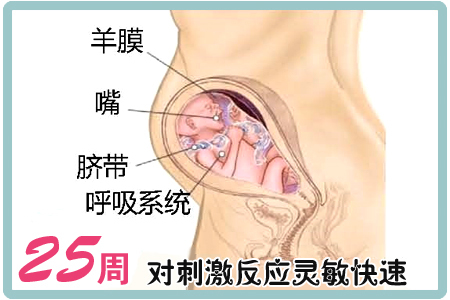

25周胎動

怀孕25周胎教 怀孕二十五周 怀孕25周胎儿图25周胎动注意事项 第二人生

怀孕25周 怀孕25周注意事项 怀孕25周胎儿图 怀孕第七个月胎儿图 怀孕计算器

怀孕25周 4天胎儿发育 怀孕科普 怀孕 太平洋亲子网

怀孕25周 怀孕二十五周胎儿图 怀孕25周吃什么 注意什么 亲子百科 太平洋亲子网

怀孕25周胎儿怀孕25周是几个月 十月怀胎 秀美网

怀孕25周 怀孕第25周胎儿图 怀孕25周四维彩超图 怀孕25周胎动 胎儿大小 好运宝贝

孕25周 胎宝宝大脑飞速发育

怀孕二十五周 怀孕25周胎儿图25周胎动注意事 孕前检查 999怀孕网

怀孕二十五周 怀孕25周胎儿图25周胎动注意事 孕前检查 999怀孕网

怀孕25周 怀孕第25周胎儿图孕25周食谱注意事项 3 孕期检查 蓝灵育儿网